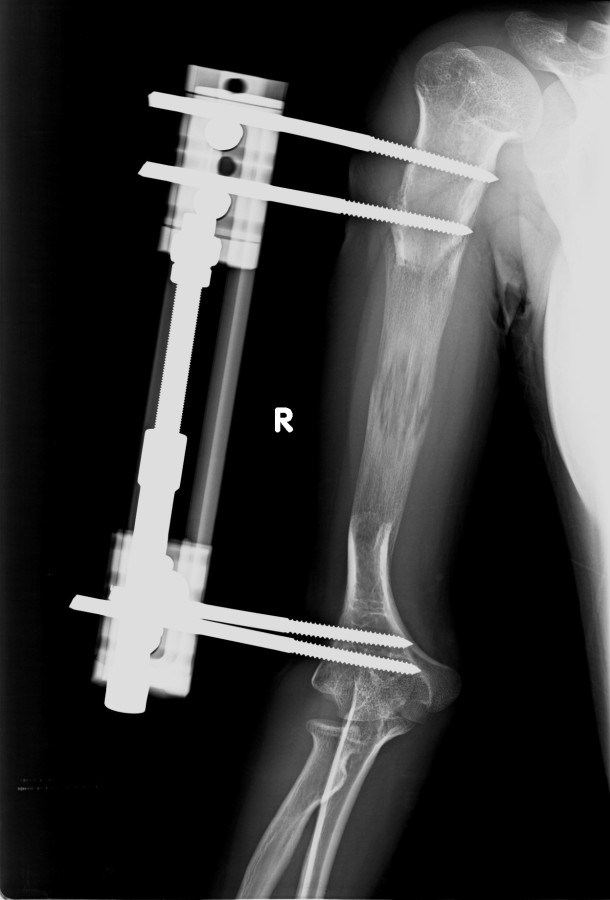

Vaka 2